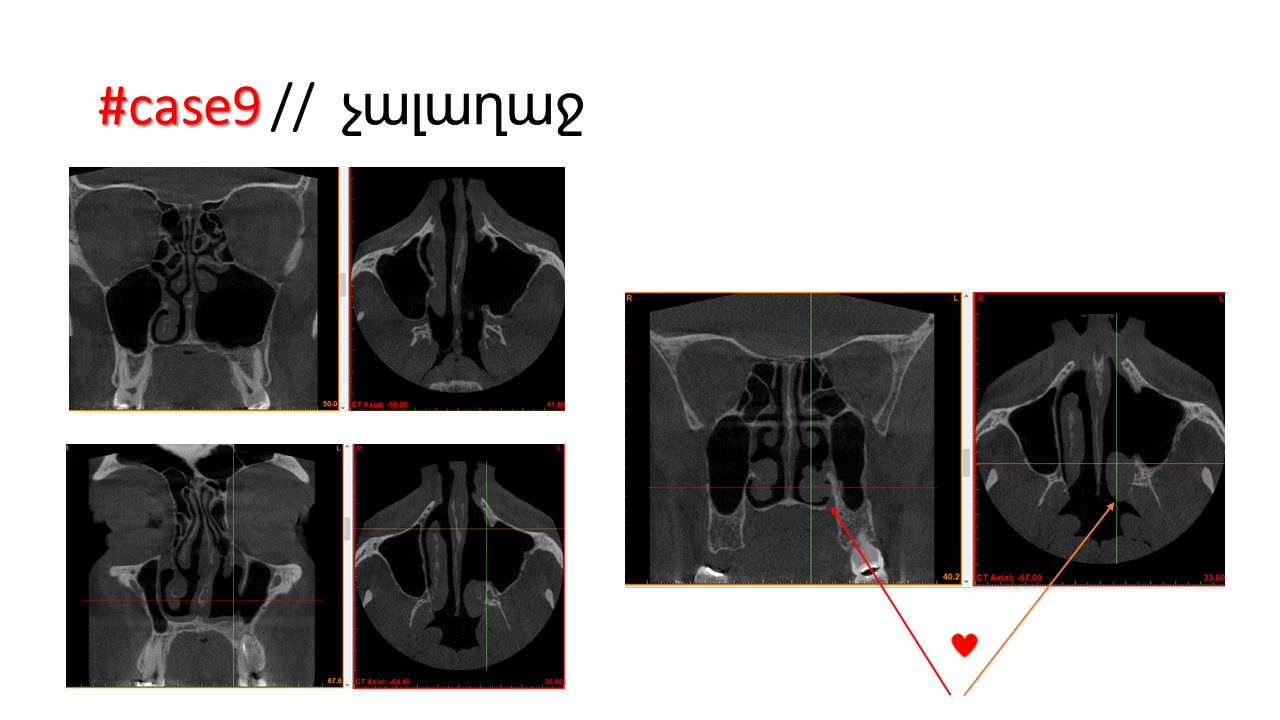

FESS Case Review and Radiologic Analysis (30.09.2016)

Case-based presentation focused on pre- and postoperative imaging in functional endoscopic sinus surgery (FESS). Includes anatomical landmarks, surgical variations, sinus pathology, and technique evaluation. Delivered by Dr. Levon Galstyan at AAOMFS.